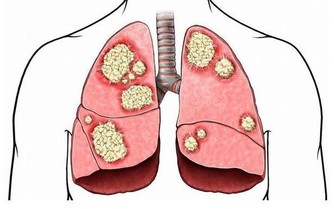

胃癌就是胃部的惡性腫瘤,此病在我國是惡性腫瘤榜首,常發生於50歲以上男性患者。

首先是手術治療,通常會切除部分或全部的胃。

其次是化療和放療。

如果是胃癌早期,治療效果還好,但是,很多胃癌被發現時已是晚期,只能對症處理,盡力延長生命、減輕痛苦,所以早發現很重要。

會的,所以要定期復查,一旦出現復發或轉移,及時治療。